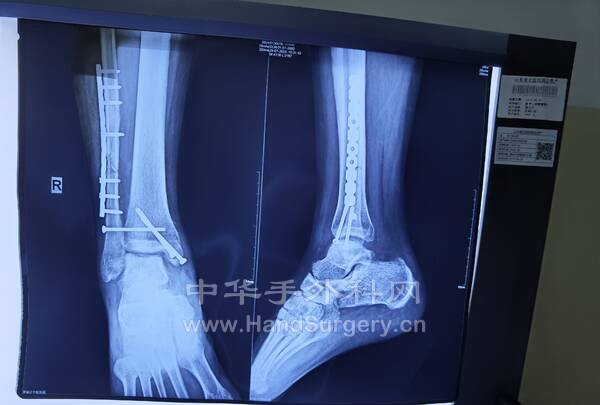

3.外院手术治疗1.5个月的患者,患者非常年轻!

2.右跟骨闭合骨折切开复位钛板内固定术:取足跟外侧改良L形切口,逐层切开显露,剥离骨膜,显露骨折端,见距下关节变形,恢复跟骨高度,宽度及距下关节面,术中拍片示贝氏角,关节面角至正常范围,放置跟骨钛板1枚及螺钉9枚,逐层闭合切口,放置引流条2枚。